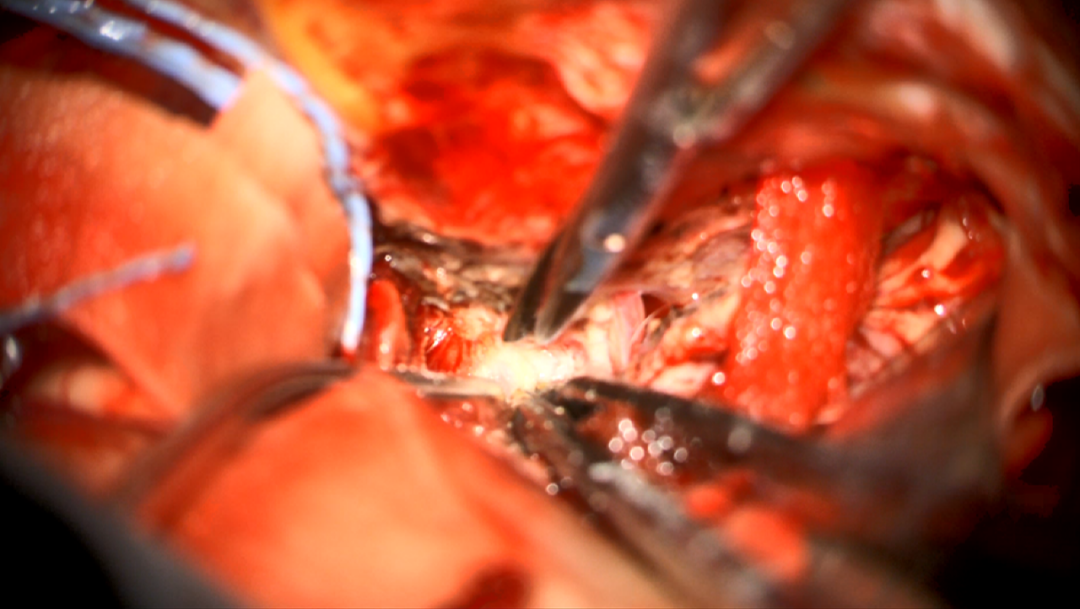

术中图片:

图21. 硬膜外入路,暴露前床突

图22. 磨除前床突

图23. 打开硬脑膜,抬起额叶,暴露肿瘤,处理肿瘤基底

图24. 分离肿瘤与颈内动脉黏连

图25. 分离肿瘤与视神经黏连

图26. 分块切除肿瘤

图27. 分离肿瘤与动眼神经黏连

图28. 分离肿瘤与大脑前动脉黏连

术后患者意识清楚,四肢活动好,对答切题,左眼视力较术前相仿,左侧动眼神经轻度麻痹,进一步康复治疗中。